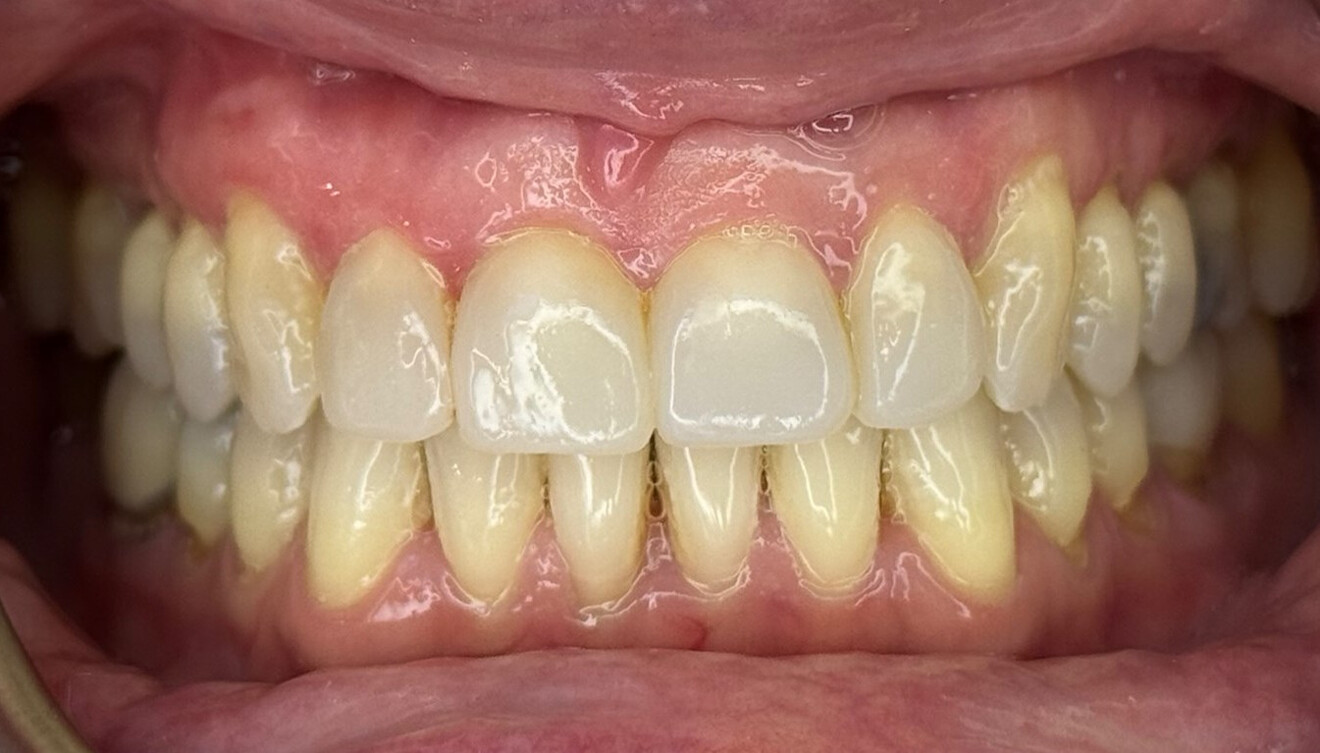

Fig. 4: Intra-oral pre-treatment photograph.